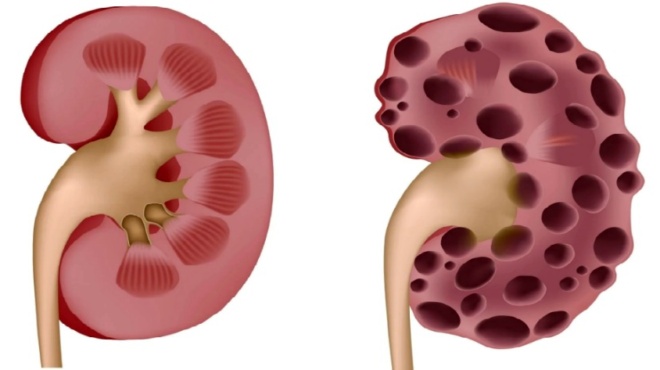

Τα νεφρά με τη βοήθεια των ούρων βοηθούν στην αποβολή των επιβλαβών ουσιών του οργανισμού. Επίσης, βοηθούν στη ρύθμιση των ηλεκτρολυτών, αλλά και της αρτηριακής πίεσης. Σε περίπ[τωση που τα προαναφερθέντα όργανα δεν λειτουργούν σωστά, τότε υπάρχουν συνέπειες. Αυτές έχουν να κάνουν με τον κίνδυνο δημιουργίας εγκεφαλικού επεισοδίου, αλλά και καρδιακής προσβολής. Παρακάτω ακολουθούν ενδείξεις, οι οποίες προαναγγέλλουν ότι τα νεφρά δεν λειτουργούν σωστά.